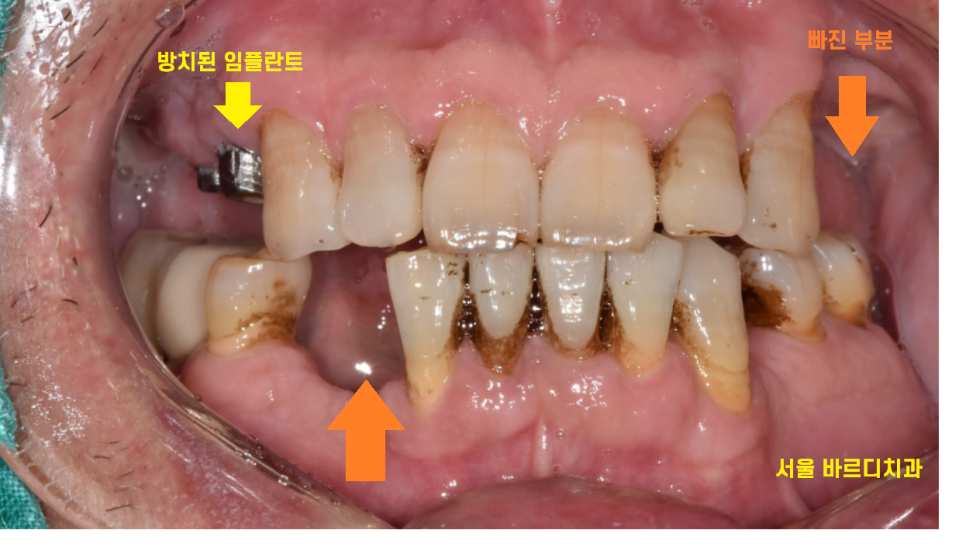

23.12.16

치아가 빠진 부분도 많고

치석도 많은 상태입니다.

환자분께서는 머리도 못올려보고

병원이 없어져서 몇년동안 치아를 방치해두셨다고 하셨습니다.